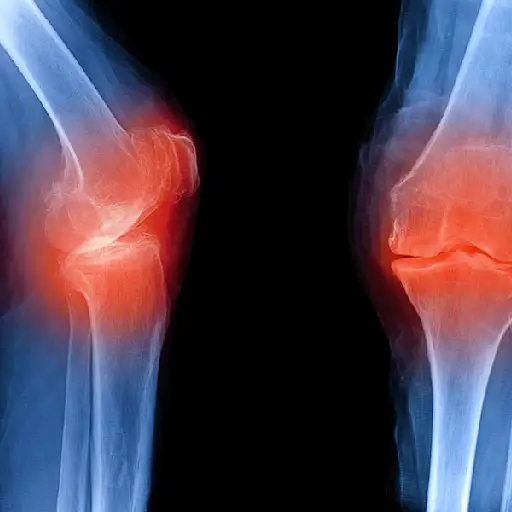

OA影响负重关节(加上手)

罗宾逊博士说,如果您在年轻人遇到任何创伤或对联合的伤害时,可以在罗斯康博士上发展。但受影响的最常见的关节是膝盖,臀部和脊柱的负重关节,以及手 - 通常是指尖关节或中指接头,或拇指的底部。在HIPS和膝盖上,OA通常是不对称的,影响一方或另一方,Ali Askari,M.D.,克利夫兰大学医院的大学医院。

Ra从手脚开始,然后击中更大的关节

RA最常在手或脚的小关节中开始,后来延长到较大的关节,如膝盖,脚踝,肘部,臀部,肩部或颈部。在手中,Ra可以瞄准手腕或指关节(底部和中间指关节,而不是顶部接头)。在脚下,它经常发生在连接脚部到脚趾的关节中。同时,除了颈椎(颈部)外,Ra从不涉及脊柱,他补充道。另一个迹象的迹象:它通常是对称的,影响身体两侧的相同关节。

OA被诊断为X射线

oa和ra都要求您给出病史并进行临床检查进行诊断。但是对于诊断OA,X射线也很重要,说Ashany博士。X射线图像可以显示骨骼之间的空间是否变得越来越窄,软骨损失的标志。他们可以揭示那些称为骨折的骨骨生长。Askari博士说,磁共振成像(MRI)也可用于检测软骨和周围组织的更详细的变化。